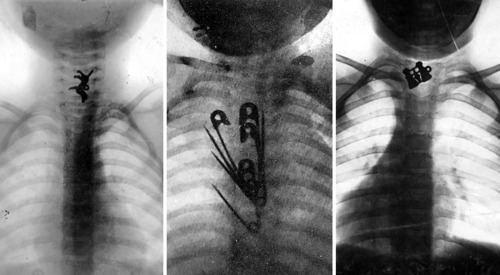

Az orvostörténet érdekes alakja dr. Chevalier Jackson gégész, aki a 19. század végén és a 20. század elején munkálkodott, és lenyelt és belélegzett, a nyelőcsőben, illetve a légcsőben megakadt tárgyakból a világ legnagyobb gyűjteményét állította össze.

Az orvosok már régóta gyakran elteszik azokat a tárgyakat vagy természetes képződményeket, amelyeket betegeikből operáltak ki, az epekőtől kezdve az agyszövetig, hol trófeaként, hol oktatási eszközként, hol különlegességként. Dr. Jackson azonban többet tett ennél: valamennyi általa eltávolított tárgyat – tűket, csavarokat, kis játékokat stb. – megőrizte, és így gyűjteménye végül több mint 2000 darabból állt.

Ezeket a nyelőcsőből vagy a légcsőből távolította el, általában anesztézia nélkül. Olyannyira ragaszkodott minden tárgyhoz, hogy egyszer még akkor sem adta oda az egyik gyermekből kivett negyeddollárost, amikor az apa halállal fenyegette – igaz, fél dollárral kárpótolta a pénzéhes szülőt.

Abban az időben nagy volt a műtétek halálozása, és kevés sebész vállalkozott arra, hogy behatoljon a nyelőcsőbe vagy a légutakba, nem is beszélve arról, hogy például nyitott biztosítótűket távolítson el onnan. Jackson sebészi tevékenysége során azonban a túlélés meghaladta a 95 százalékot.